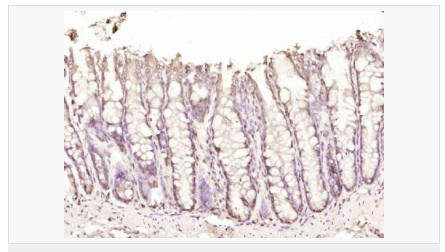

產(chǎn)品介紹his gene encodes a basic, proline-rich, 15-kD protein. The protein acts as a positive mediator of programmed cell death that is induced by interferon-gamma.

Negative regulator of autophagy. Involved in mediating interferon-gamma-induced cell death.

Phosphorylated. Phosphorylation by MTOR inhibits the suppressive activity of DAP toward autophagy.